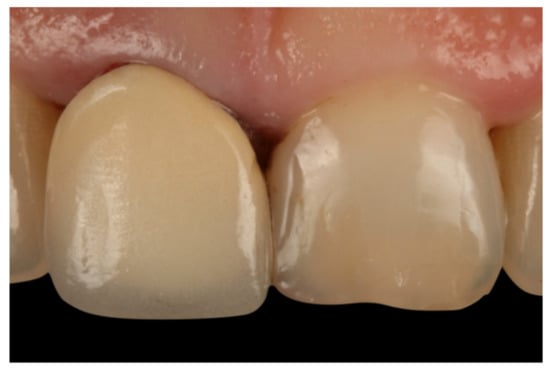

- Agustín-Panadero, R.; Solá-Ruíz, M.F. Vertical preparation for fixed prosthesis rehabilitation in the anterior sector. J. Prosthet. Dent. 2015, 114, 474–478. [Google Scholar] [CrossRef] [PubMed]

- Agustín-Panadero, R.; Serra-Pastor, B.; Fons-Font, A.; Solá-Ruíz, M.F. Prospective Clinical Study of Zirconia Full-coverage Restorations on Teeth Prepared with Biologically Oriented Preparation Technique on Gingival Health: Results After Two-year Follow-up. Oper. Dent. 2018, 43, 482–487. [Google Scholar] [CrossRef] [PubMed]